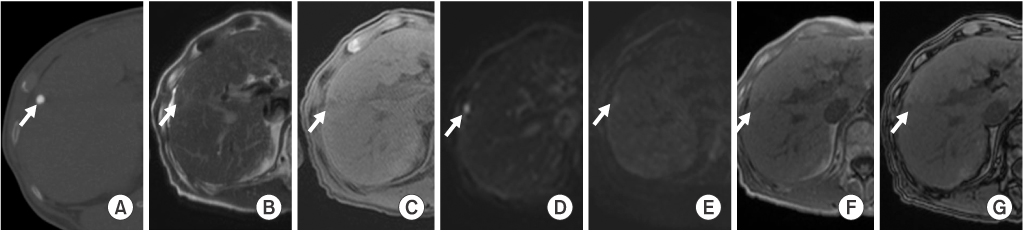

Among the 12 partial LHCCs in group B, six LHCCs (50%) revealed high SI, and four LHCCs (33%) revealed mixed SI on T2WI. Six LHCCs (50%) revealed low SI, and four LHCCs (33%) revealed mixed SI on T1WI. At b values 0, 50, 400, and 800 high SI was observed on DWI in six, seven, seven, and six LHCCs, respectively. Ten LHCCs (83%) revealed decreased SI when compared to liver parenchyma at higher DWI b values of 400 and 800. Six LHCCs (50%) revealed high SI on inphase GE, and seven LHCCs (58%) revealed low SI on out-of-phase GE. None of the 12 LHCCs were enhanced on dynamic contrast-enhanced images (Table 1, Fig. 3).

Fig. 3

MR images of a 57-year-old patient with a 2.3×2.3 cm-sized hepatocellular carcinoma with partial lipiodol uptake in hepatic segment 6. Hepatocellular carcinoma (arrows) shows partial uptake of lipiodol on precontrast computed tomography with bone window setting (A), high signal intensity on T2-weighted images (B), and low signal intensity on T1-weighted images (C). On diffusion-weighted images, the lesion reveals high signal intensity at a lower b factor (b=0) (D) and decreased signal intensity at a higher b factor (b=800) (E) images. It shows low signal intensity on in-phase (F) and out-of-phase (G) gradient-echo images. Hepatocellular carcinomas is not enhanced on dynamic contrast-enhanced arterial phase (H), portal phase (I) or 20-minute delayed phase (J) images.

Fig. 3 MR images of a 57-year-old patient with a 2.3×2.3 cm-sized hepatocellular carcinoma with partial lipiodol uptake in hepatic segment 6. Hepatocellular carcinoma (arrows) shows partial uptake of lipiodol on precontrast computed tomography with bone window setting (A), high signal intensity on T2-weighted images (B), and low signal intensity on T1-weighted images (C). On diffusion-weighted images, the lesion reveals high signal intensity at a lower b factor (b=0) (D) and decreased signal intensity at a higher b factor (b=800) (E) images. It shows low signal intensity on in-phase (F) and out-of-phase (G) gradient-echo images. Hepatocellular carcinomas is not enhanced on dynamic contrast-enhanced arterial phase (H), portal phase (I) or 20-minute delayed phase (J) images.